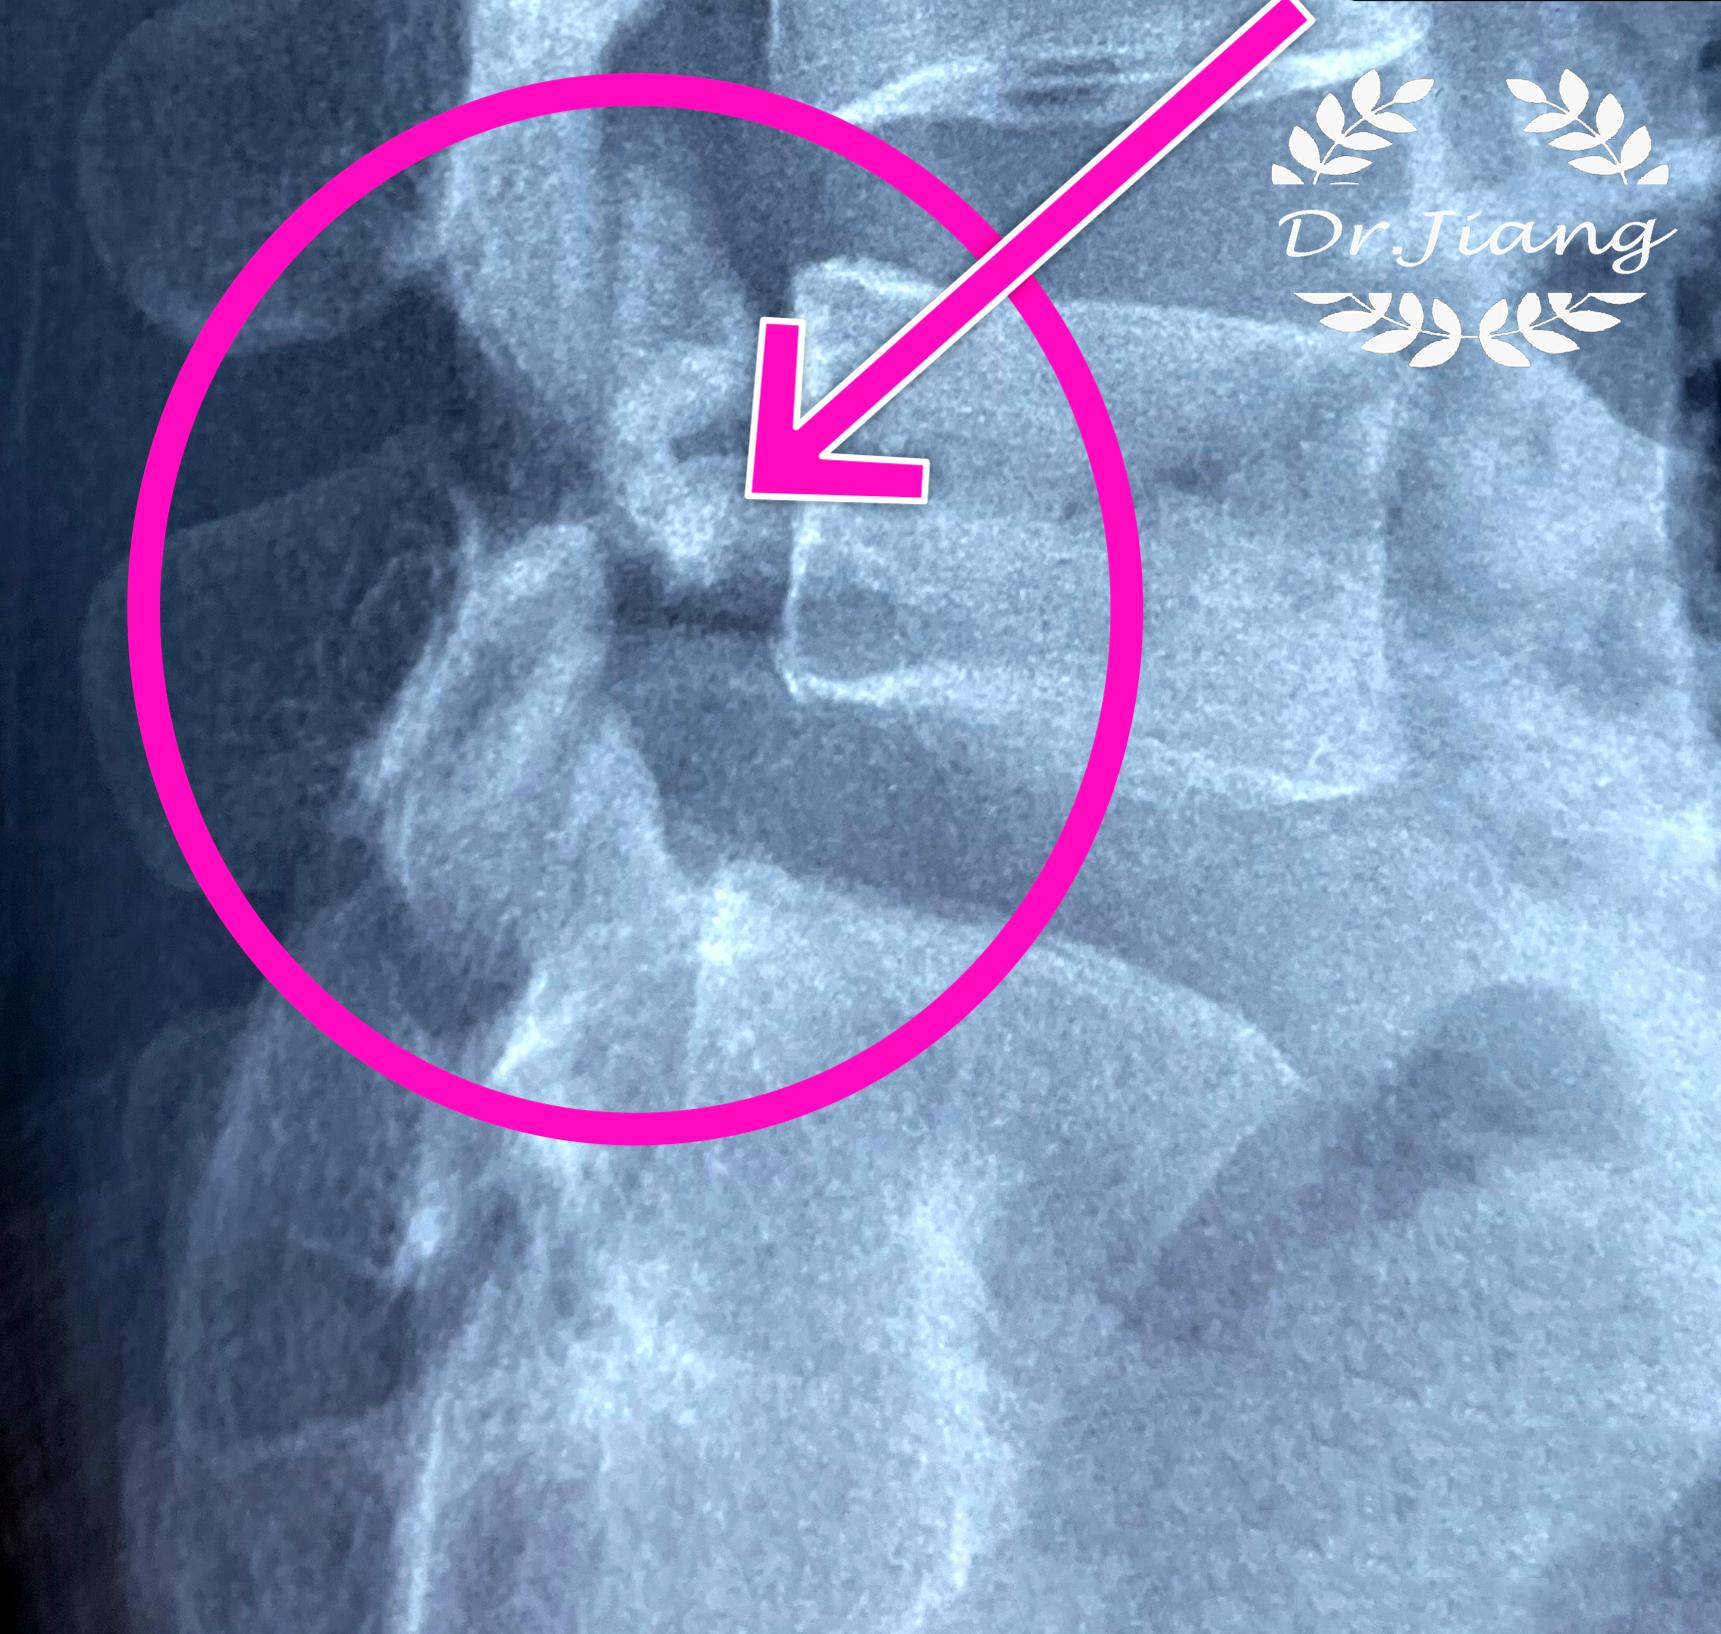

当峡部断裂时,临床称为“苏格兰狗颈断裂征”或“长颈犬征”是峡部裂斜位X片典型表现。

腰椎峡部裂是指腰椎一侧或两侧峡部骨质缺损不连续,好发于L4和L5节段。

腰5峡部裂